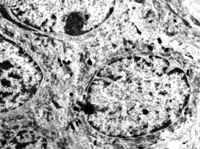

5-2-8 傷后第10天,皮膚附件上皮細(xì)胞成簇分布,核仁邊集,內(nèi)質(zhì)網(wǎng)擴(kuò)張,胞質(zhì)內(nèi)含較多張力原纖維  TEM×6000